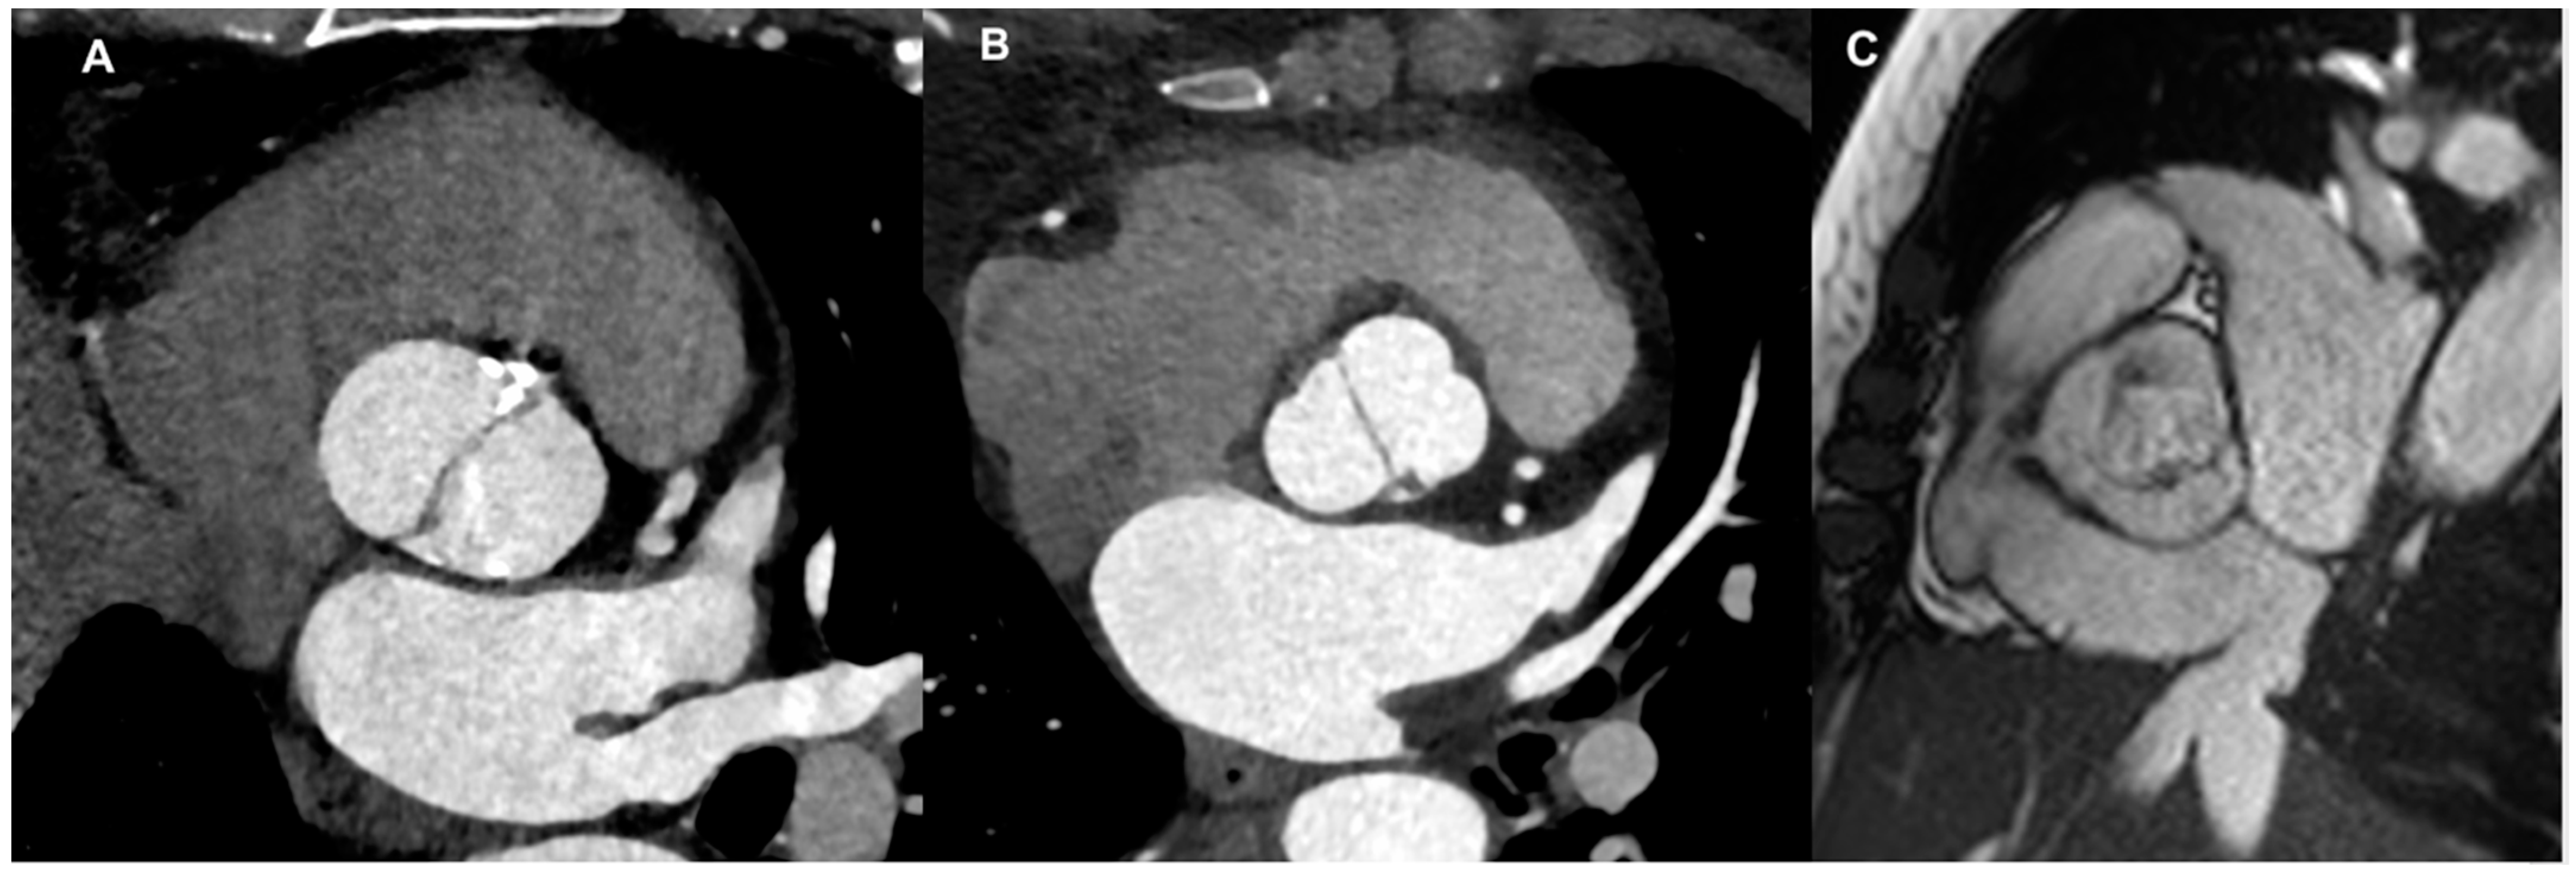

There are multiple nomenclatures and classifications for the BAV condition [3,4]. The most common used is Sievers classification system, in which three mayor types were identified: type 0 (no raphe in the valve) (Figure 1A), type 1 (only one raphe in the valve) (Figure 1B), and type 2 (two raphes in the valve). Based on this classification, the most prevalent type is type 1, representing approximately 90% of patients [5]. Depending on the position of the raphe in relation to the coronary sinuses, types 1 and 2 are categorized as left (L), right (R), and none (N) types. A new nomenclature/classification system was published, derived from an international consensus statement and representing the combined efforts of international BAV experts [4]. According to this further classification, three BAV types are identified—the fused BAV, the two-sinus BAV, and the partial-fusion BAV (Figure 1C)—each with different phenotypes [6]. The fused BAV is the most common, accounting for about 90–95% of cases [3]. It is characterized by two of the three cusps appearing fused or joined within three distinguishable aortic sinuses, resulting in two functional cusps (one fused or conjoined and the other non-fused) that typically vary in size and shape. Within the fused type, there are three specific BAV phenotypes: right–left cusp fusion, right–non (non-coronary) cusp fusion, and left–non (non-coronary) cusp fusion. The right–left cusp fusion phenotype is the most common, occurring in 70–80% of American, European, and Asian populations [3].

Figure 1. Different BAV types: (A) Sievers type 0 (valve with no raphe) by CT scan; (B) Sievers type 1 (valve with only one raphe) by CT scan; (C) partial-fusion BAV by CMR cine-sequence.